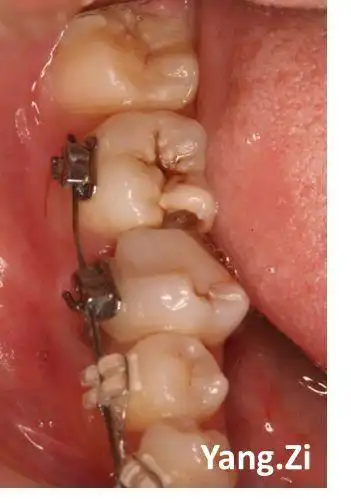

下颌第二磨牙c形根管

下颌第二磨牙c3型弯曲根管一例

右下第二磨牙慢性根尖炎一例